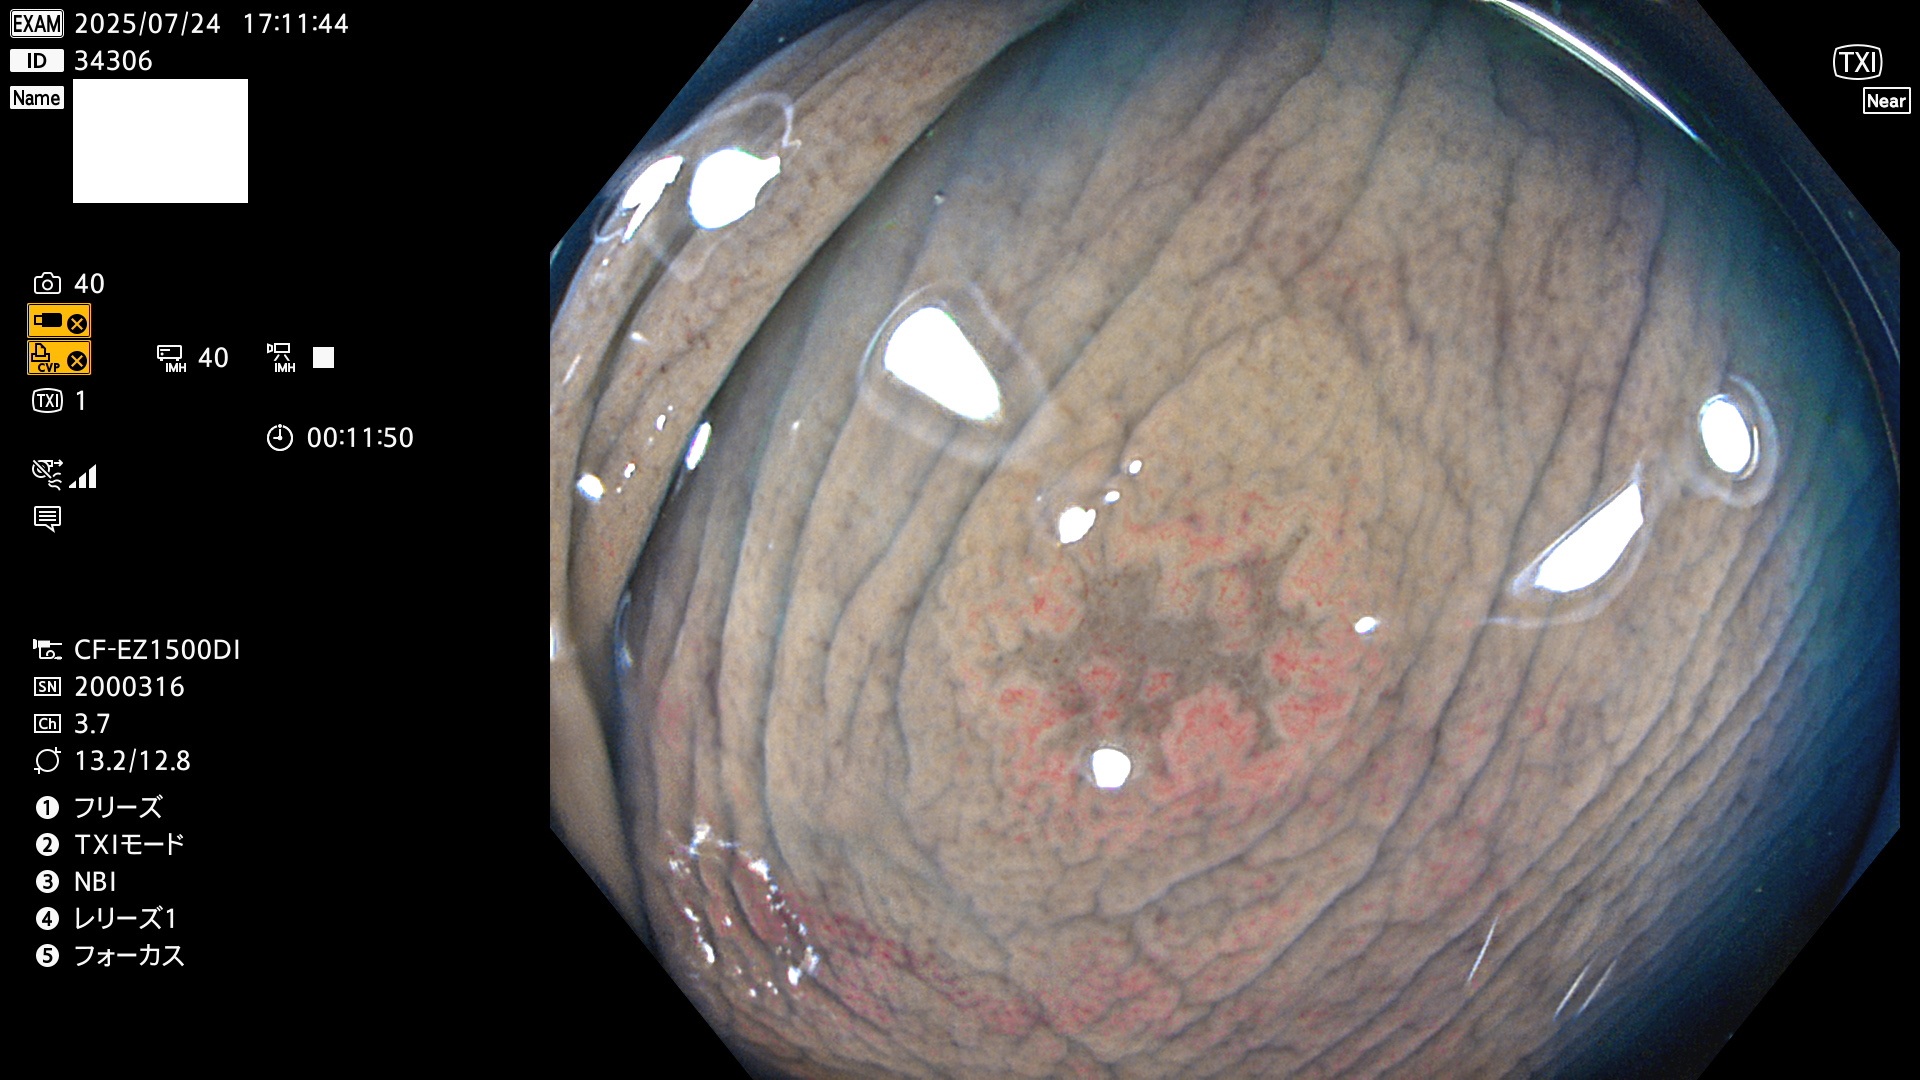

完全に平坦な物をUb、陥凹している物をUcと呼びます。Ubは認識が困難で、Ucはびらん(炎症)と紛らわしいために見落とされやすく、「内視鏡後・大腸癌」の原因になります。

専門的)Uc=De Novo癌? 内視鏡の解像度が低かった時代、このような説もありました。しかし今日の高精度内視鏡では良性の微小なUc型腺腫(APC遺伝子異常の腺腫)が日常的に見つかります。Ucこそが多段階発癌(Adenoma-Carcinoma Sequence)のMain Routeです。

2025年7月24日〜7月27日の4日間(40件)15個 (Uc_ADR=15個/40人=38%)